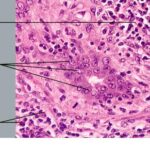

Angiolymphoid hyperplasia with eosinophilia (ALHE) shows characteristic histologic features, including a proliferation of small blood vessels, many of which are lined by enlarged endothelial cells with uniform ovoid nuclei and intracytoplasmic vacuoles. These distinctive endothelial cells have been described as having a cobblestone appearance. In addition, a perivascular and interstitial infiltrate composed primarily of lymphocytes and eosinophils (see the image below) is present. Eosinophils typically comprise 5-15% of the infiltrate. Rarely, they can account for as much as 50% of the infiltrate. Occasionally, the infiltrate is devoid of eosinophils. Lymphoid aggregates with or without follicle formation are typical.